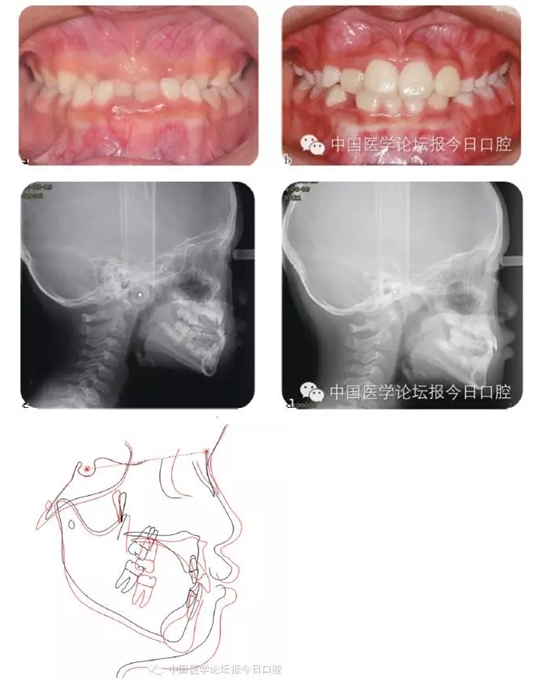

傳統(tǒng)的功能矯形概念認(rèn)為應(yīng)在兒童青春發(fā)育高峰前期開始矯治。對(duì)于骨性Ⅲ類矯形治療的開始時(shí)間,國(guó)內(nèi)外一直存在爭(zhēng)議。

華西兒童早期矯治???,總結(jié)本科室Ⅲ類骨性矯治的療效,認(rèn)為Ⅲ類骨性畸形的矯形矯治在第一恒磨牙萌出時(shí)(6歲)開始,比在青春發(fā)育高峰前期時(shí)(9歲)開始,能得到更多的骨性改變。Ⅲ類骨性畸形的早期功能矯治,見圖4。

圖4 骨性Ⅲ類錯(cuò)患兒的早期矯治前、后;后續(xù)保持一直持續(xù)至兒童生長(zhǎng)發(fā)育結(jié)束

必須強(qiáng)調(diào)的是,早期功能矯形治療必須保持到恒牙列初期(12歲),以維持矯形治療的效果,避免由于遺傳因素導(dǎo)致錯(cuò)牙合畸形復(fù)發(fā)。